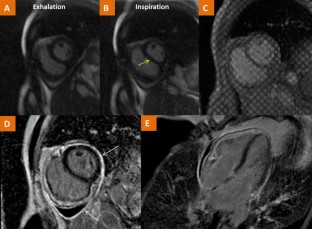

Figure 1